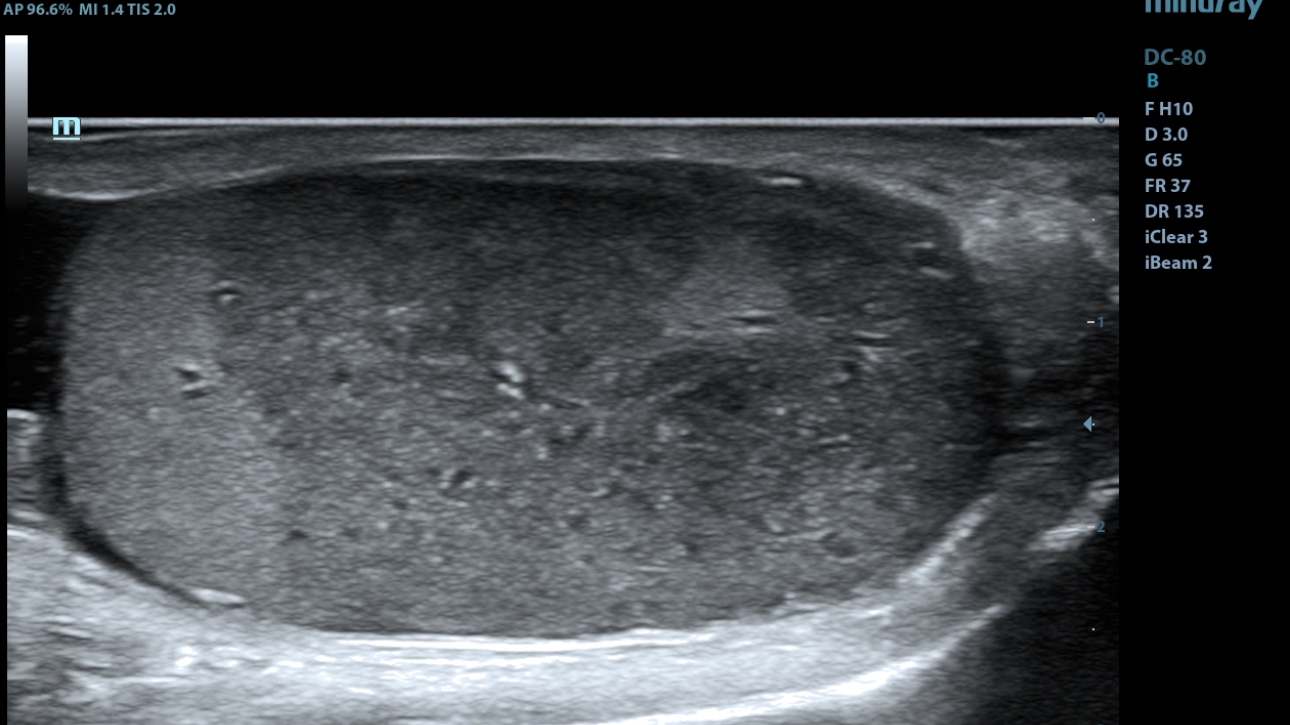

eXpress Clarity

More clarity at hand

To achieve excellent images with minimal effort is always the highest clinical priority and Mindray's endless pursuit. With continuous innovation of imaging and transducer technologies, X-Insight delivers express clarity as soon as the transducer touches the body.